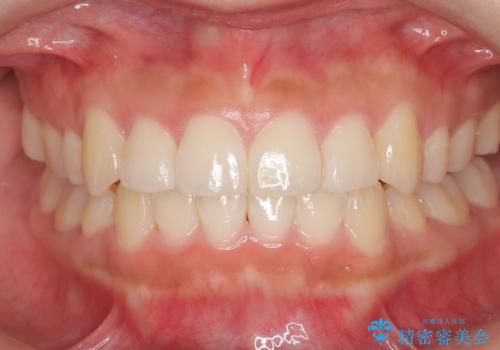

- 1年1ヶ月

前歯のガタツキを改善する治療法として、マウスピース矯正が適していることが多いです。

マウスピース矯正は、金属製のブラケットやワイヤーを使用せずに、透明なマウスピースを装着して歯を移動させる方法です。そのため、目立たず、痛みも少ないです。